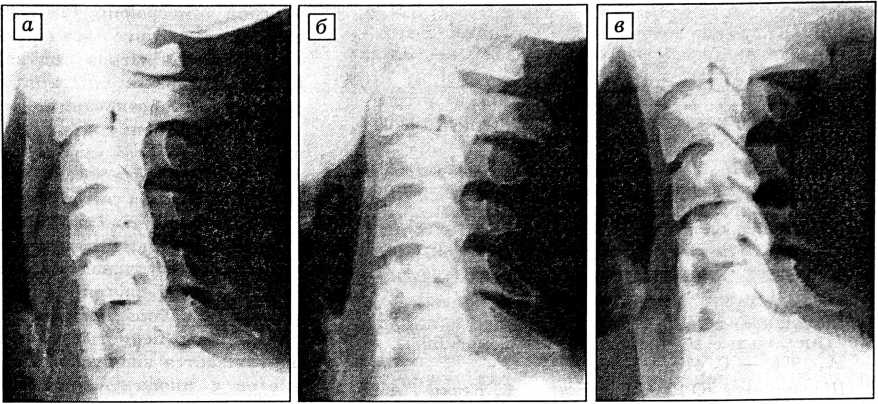

В качестве иллюстрации приводим данные рентгенологического наблюдения больного Б., 17 лет, которому было выполнено замещение поврежденного тела С6 позвонка (см. рисунок). Обращает на себя внимание отсутствие известной периодичности в формировании костного блока. Процесс протекает постепенно, и формирующийся блок достигает плотности соседней костной ткани без промежуточного периода хрящевого (фиброзного) блока.

Рентгенологические данные были подтверждены КТ-денситометрией. Средние показатели плотности образующегося блока в единицах Хаусфилда нарастали постепенно, сравниваясь с показателями соседних участков здоровой кости ко времени, соответствующему появлению рентгенологической картины костного блока.

Рентгенограммы шейного отдела позвоночника больного Б. после резекции тела С6 позвонка и спондилодеза по предложенной методике: а — через 7 дней после операции; б — через 6 нед; в — через 9 нед.